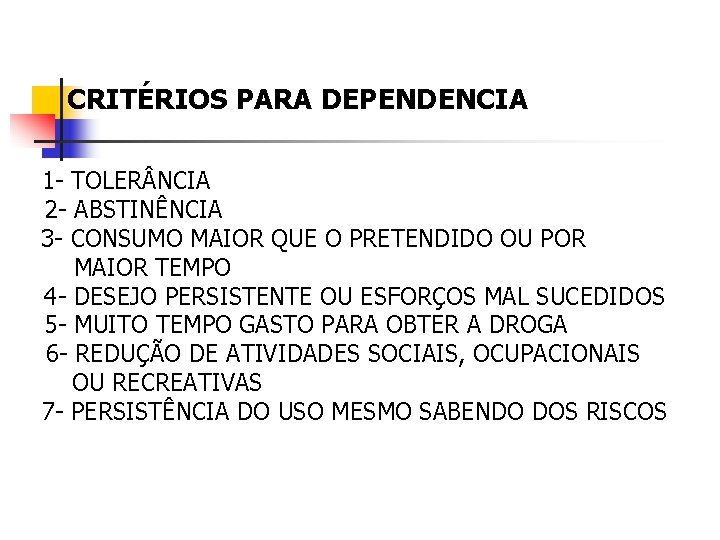

CRITÉRIOS PARA DEPENDENCIA 1 - TOLER NCIA 2 - ABSTINÊNCIA 3 - CONSUMO MAIOR QUE O PRETENDIDO OU POR MAIOR TEMPO 4 - DESEJO PERSISTENTE OU ESFORÇOS MAL SUCEDIDOS 5 - MUITO TEMPO GASTO PARA OBTER A DROGA 6 - REDUÇÃO DE ATIVIDADES SOCIAIS, OCUPACIONAIS OU RECREATIVAS 7 - PERSISTÊNCIA DO USO MESMO SABENDO DOS RISCOS